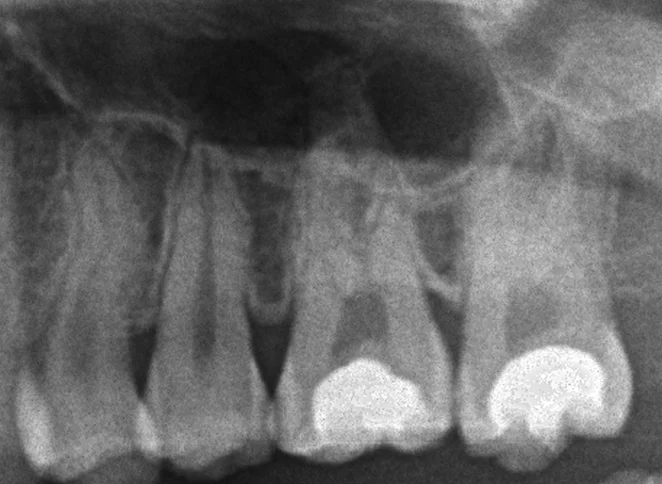

この歯のレントゲンがこちらですが、

実は前後とも神経が一層出るほどのギリギリな虫歯でした。

今回の方も、幸い神経の温存も成功しているようで、ダイレクトボンディング自体も欠けたりもせずに順調に使用できているようで良かったです。